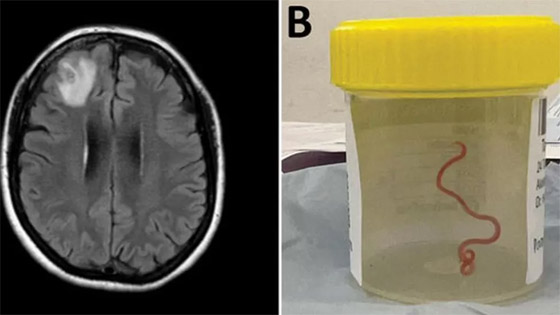

وأدخلت المريضة، مستشفى محلي في نيوز ساوث وليز في أواخر يناير 2021 بسبب آلام في البطن وإسهال وسعال جاف مستمر وحمى وتعرق ليلي. وتفاقمت الأعراض في 2022 لتشمل النسيان والاكتئاب. ثم أدخلت مستشفى كانبيرا، حيث كشفت فحوص الرنين المغناطيسي لدماغها عن وجود تشوهات تتطلب عملية جراحية. لتجري هاري بريا، الجراحة وتكتشف وجود هذه الدودة الحية.

عقب استخراج الدودة أرسلت إلى أحد العلماء المتخصصين الذي أكد أنها دودة تتواجد في الثعابين. وقال تقرير الغارديان إنها أول حالة لاكتشاف هذه الطفيلي في البشر، موضحا أن المريضة تعيش قرب بحيرة تكثر فيها إحدى أنواع الثعابين. ورجح الأطباء والعلماء الذين درسوا حالتها أنها ربما وصلتها الدودة من خلال براز الثعابين في العشب.